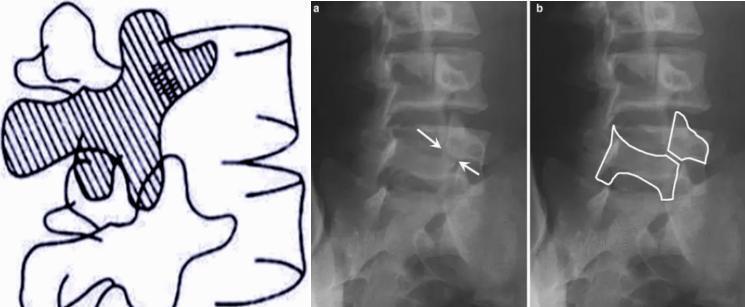

青少年腰椎峽部裂

腰椎峽部裂是指腰椎的一側或雙側椎弓上下關節(jié)突與橫突移行區(qū)骨質不連續(xù)或骨質缺損,也稱峽部不連或椎弓崩裂。通常是在先天發(fā)育異?;蚬琴|薄弱的基礎上,腰椎峽部受到反復應力作用致使峽部疲勞骨折。腰椎峽部裂好發(fā)于L5,其次是L4,亦可L4和L5同時發(fā)病,其他節(jié)段較少發(fā)病,是造成青少年下腰痛的重要原因之一。腰椎峽部裂的典型癥狀表現(xiàn)在腰椎斜位X片上,由于人體腰椎在腰椎斜位X片中形似蘇格蘭狗,“蘇格蘭狗”以腰椎椎板為身體,上、下關節(jié)突為腿,椎弓根為眼睛。而“蘇格蘭狗”的頸部對應的正是腰椎峽部,因此當峽部斷裂時,臨床稱為“蘇格蘭狗頸斷裂征”或“長頸犬征”。青少年腰椎峽部裂早期一般無臨床癥狀。隨著腰椎的繼續(xù)退變,約有10%的個體出現(xiàn)反復發(fā)作的軸性腰痛、臀部及大腿后部疼痛等癥狀,若引發(fā)腰椎滑脫可出現(xiàn)下肢相應皮節(jié)區(qū)的疼痛、麻木癥狀。????青少年腰椎峽部裂的治療應首先以保守治療為主。若通過嚴格的保守治療6個月以上臨床癥狀無明顯緩解,或出現(xiàn)腰椎間盤突出癥、腰椎管狹窄癥的臨床表現(xiàn),亦或在影像學上發(fā)現(xiàn)病變椎體有滑脫傾向,則需考慮手術治療。????常用的手術方式有椎弓根螺釘-椎板鉤固定法、Buck峽部螺釘固定法。椎間融合術主要用于腰椎峽部裂合并Ⅱ度及以上腰椎滑脫,或伴有腰椎間盤退變及腰椎穩(wěn)定性差的患者,青少年腰椎峽部裂一般無滑脫存在或僅有輕度滑脫,故椎間融合術很少用于治療青少年腰椎峽部裂。微創(chuàng)手術因創(chuàng)傷小、出血少、術后恢復快等優(yōu)點,近年來越來越受到廣大醫(yī)生的青睞和患者的認可。